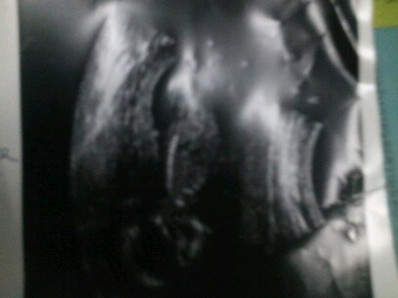

ท้องแรก 4เดือน

ท้องแรกค่ะ 17w ท้องเล็ก. ผิดปกติมั้ยค่ะ

ปกติค่ะแม่ท้องเเรกจะเล็ก ไปตามสรีระของเรา คนท้องเล็กส่วนมากลูกตัวใหญ่นะค่ะ